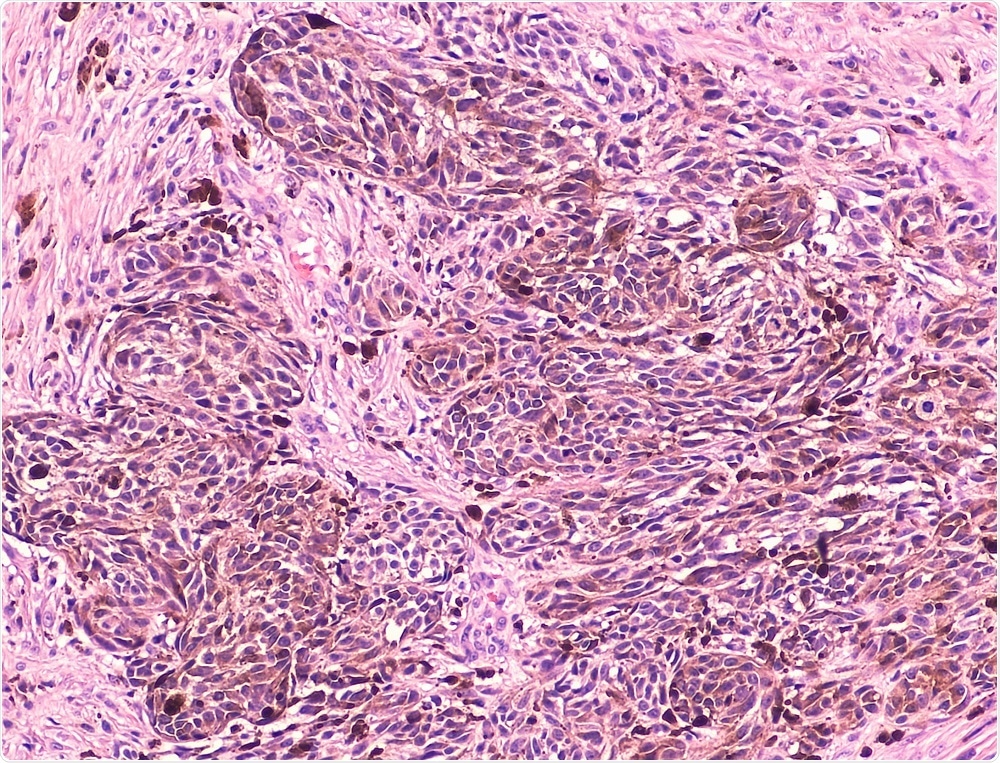

H&E stain of melanoma cells in skin

Image Credit: David Litman / Shutterstock.com